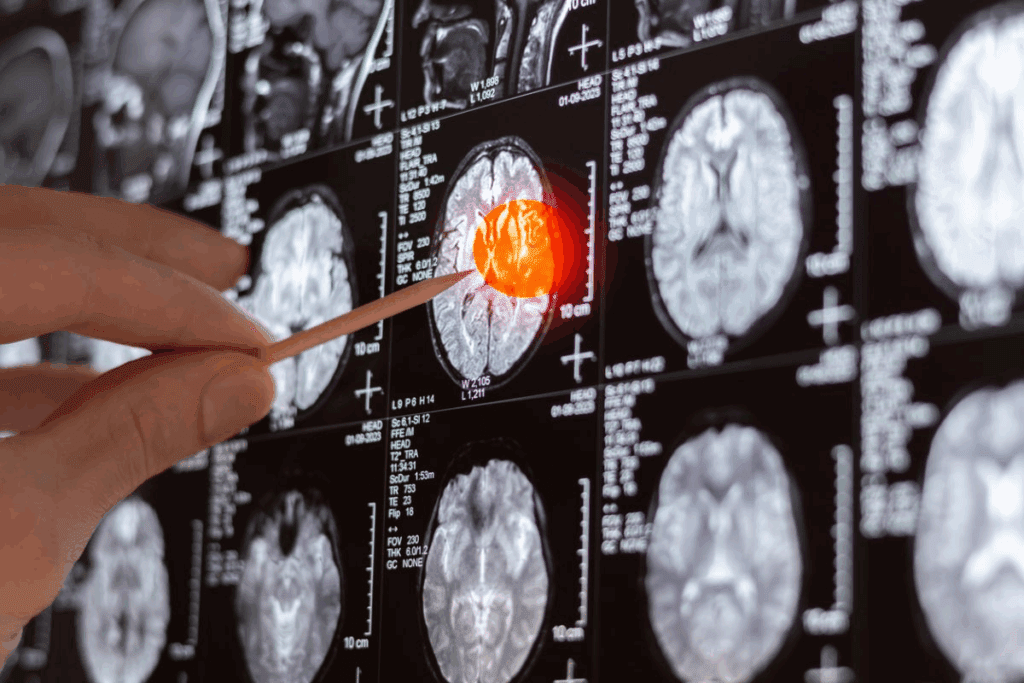

Interpreting CT Scan Results: What Do Brain Tumors Look Like?

Reading CT scans correctly is key to spotting brain tumors and what they mean. CT scans show detailed brain images. This helps doctors find any oddities.

Common Appearances of Different Tumor Types

Brain tumors look different on CT scans. This depends on their size, type, and where they are. Some tumors are clear and have sharp edges. Others are harder to see and spread out.

Meningiomas look like dense, round shapes near the brain’s surface. They stick to the dura mater. On the other hand, glioblastomas are irregular and have dead spots and swelling around them.

| Tumor Type | Typical Appearance on CT | Contrast Enhancement |

| Meningioma | Dense, rounded mass near brain surface | Often shows strong enhancement |

| Glioblastoma | Irregular, heterogeneous mass | Variable enhancement with areas of necrosis |

| Pituitary Adenoma | Sellar or suprasellar mass | Typically shows enhancement |

It’s important to know the terms in these reports. “Hypodense,” “hyperdense,” and “isodense” describe how the tumor looks compared to the brain. The report might also mention if the tumor shows up well with contrast. This can tell us about the tumor’s blood supply and if it might be cancerous.